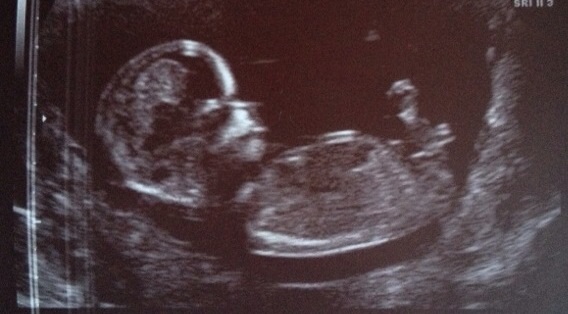

Hiya! My pic is 13 weeks any guesses on boy or girl? Thanks :-))))

My first thought was boy, but the more I look the more I don't think the actual whole nub is in the pic.....tough one! Congrats on bubba tho :)

Boy :-)

Thanks for takin a look n havin a guess :-) any reason you think boy mamashan or just a guess? I find out Saturday so I'll be able to let u know :-)